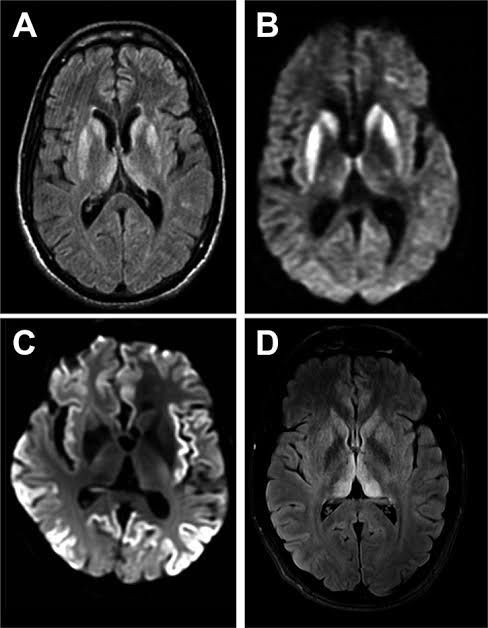

Classic CJD is a human prion disease. It is a neurodegenerative disorder with characteristic clinical and diagnostic features. This disease is rapidly progressive and always fatal. Infection with this disease leads to death usually within 1 year of onset of illness